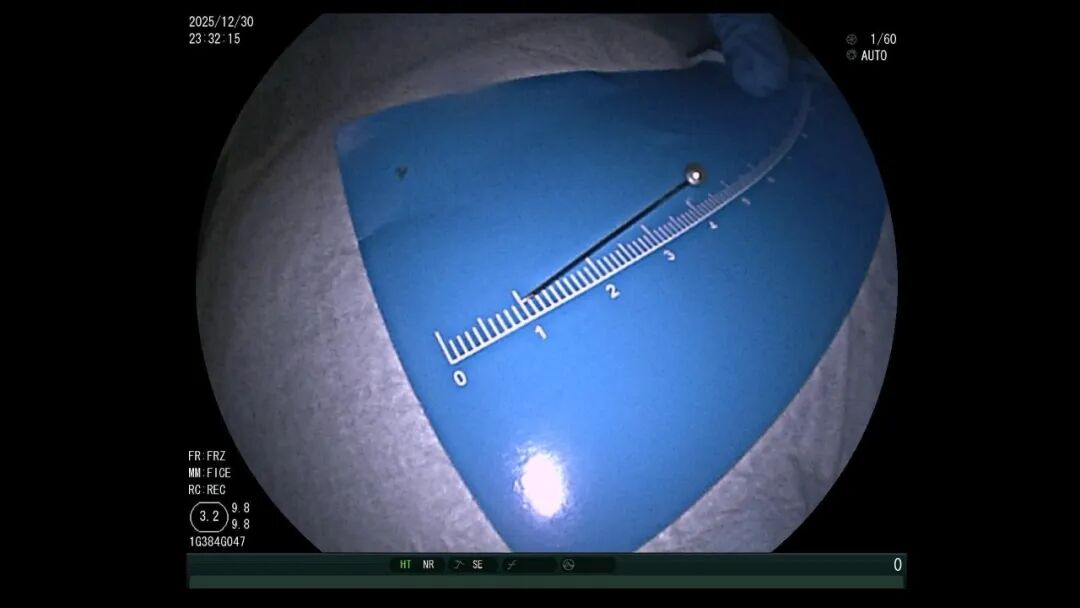

只需要简单的工具 就能制作神奇的暗器! 百发百中让很多小孩跃跃欲试 然而就在最近 深圳一11岁男孩却因为这款游戏 进了医院 据南方科技大学深圳医院消息 一天晚上,一名11岁男孩被家长紧急送医 就在不久前 男孩刚刚吞下一根大头针 据悉,11岁的小明在家自制吹箭玩具 “呼”的一声 不小心把一枚大头针吸进嘴里 慌乱中竟直接吞了下去! “孩子说喉咙有点疼 我们立马带他去医院” 当地医院的CT检查显示,大头针在胃腔 但怎么取出来困难重重: 孩子刚吃完牛肉面,胃里全是食物残渣 无法全麻 也无法内镜取出 医生评估后建议立即转诊 家长立马带着孩子 一路狂奔到南方医科大学深圳医院 消化内科团队立刻开通绿色通道 摆在医生面前的 有三大难题: 麻醉无法用: 孩子胃里全是未消化的食物,全麻极易发生食物误吸,堵塞气道,只能选择普通内镜操作,全程要靠孩子配合。 {jz:field.toptypename/}异物找不着: 3.5厘米的大头针混在胃里的食物残渣中,要把它找出来,难度堪比大海捞针。 操作风险高: 大头针尖锐、易滑动,传统的异物钳、网兜根本抓不住,一旦操作不当,针尖可能划伤食管黏膜,引发穿孔、出血。 面对这些棘手情况,消化内科迅速联合儿科和普外科制定方案,经过30分钟的专注搜寻,医生终于锁定了大头针的针尖位置——它正静静“躺”在食物残渣中,银色的针尖格外显眼。 一开始,医生尝试用异物钳、网兜抓取,但大头针太滑,几次尝试都失败了。紧急调整方案后,医生改用圈套器,在透明帽的辅助下,小心翼翼地将大头针调整为竖直方向,避免取出时横向划伤食管。 医生一边指导孩子配合,一边稳稳操控圈套器,将大头针牢牢固定。随着内镜缓缓退出,大头针终于被完整取出,全程未造成任何黏膜损伤。